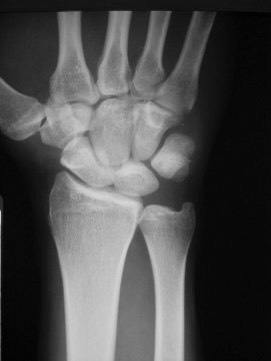

This X-ray shows the orientation of the bones in the wrist when there is a severe scapholunate ligament injury.  The scapholunate ligament is completely disrupted and allows the scaphoid and lunate to completely separate from one another.  Often the findings are not this obvious and more sophisticated  imaging studies may be necessary to make the diagnosis.

A chronic scapholunate dissociation injury can start causing arthritis to develop in the wrist.  This type of arthritis start affecting the joint between the scaphoid and radius first.  Treatment is directed at this problem to get relief of symptoms.